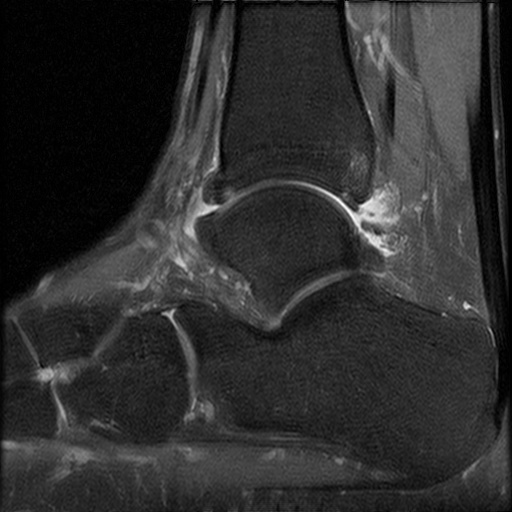

患者,男,28岁,有踝关节扭伤史,患者10天前扭伤致左踝疼痛伴活动受限。查体:左踝关节轻度肿胀,关节缘广泛性压痛,未扪及骨擦音及骨擦感,局部皮肤无瘀青、无皮损,外翻应力试验阳性,抽屉试验阳性,肢端感觉及血运正常。

患者行关节镜下距腓前韧带修补术,术后恢复良好。